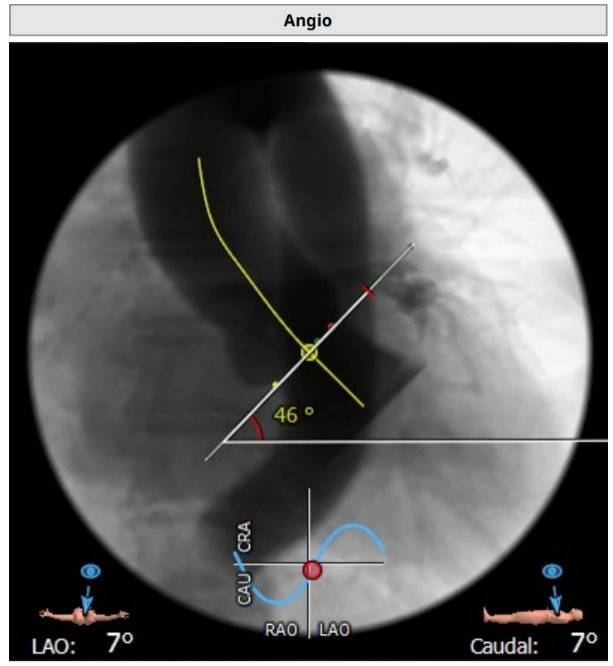

升主动脉未见明显扩张,心脏角度:46°

在放射科,超声科和麻醉科的通力协作下,顺利完成了术前准备,术者团队在术中谨慎建立轨道,根据主动脉根部造影的结果观察瓣叶活动情况、瓣环结构。

选择20 mm球囊进行预扩,造影提示腰征不明显,存在瓣周漏。瓣叶被掀至STJ,结合术前评估考虑存在冠脉风险,在6F指引导管辅助送入Guidzilla导管实施冠脉保护。选择植入VenusA-Plus® L23型号瓣膜。

主动脉根部造影